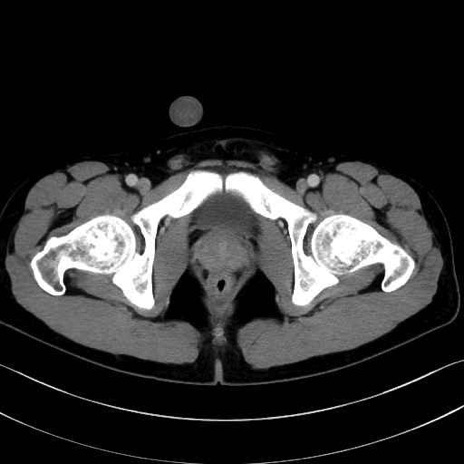

精嚢(seminal vesicle)のCT画像における解剖

症例

【症例】20歳代 男性 スクリーニング